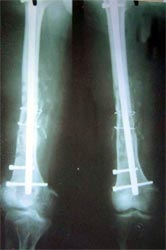

病例一、患者22岁,股骨中下1/3骨折骨不连2年,明显畸形。

X线片显示钢板螺钉已经松脱,固定失败,断端骨折端硬化

我们用髓内钉内固定后保证早期稳定性,植骨补充成骨所需基质,骨生长因子和骨髓细胞的植入,可分化成为骨痂组织,有效促进了骨不连的愈合